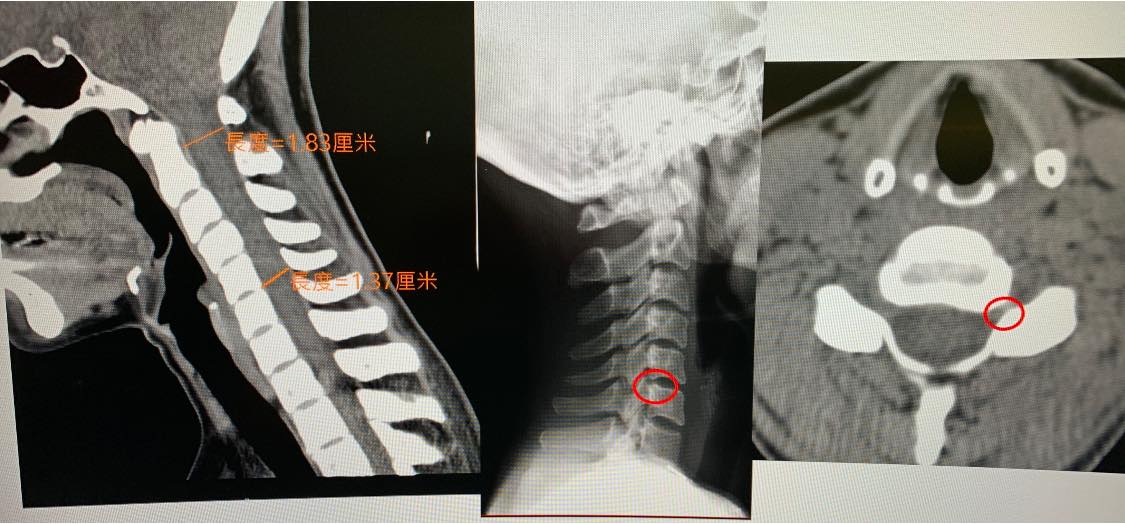

#電腦斷層顯示椎管狹窄